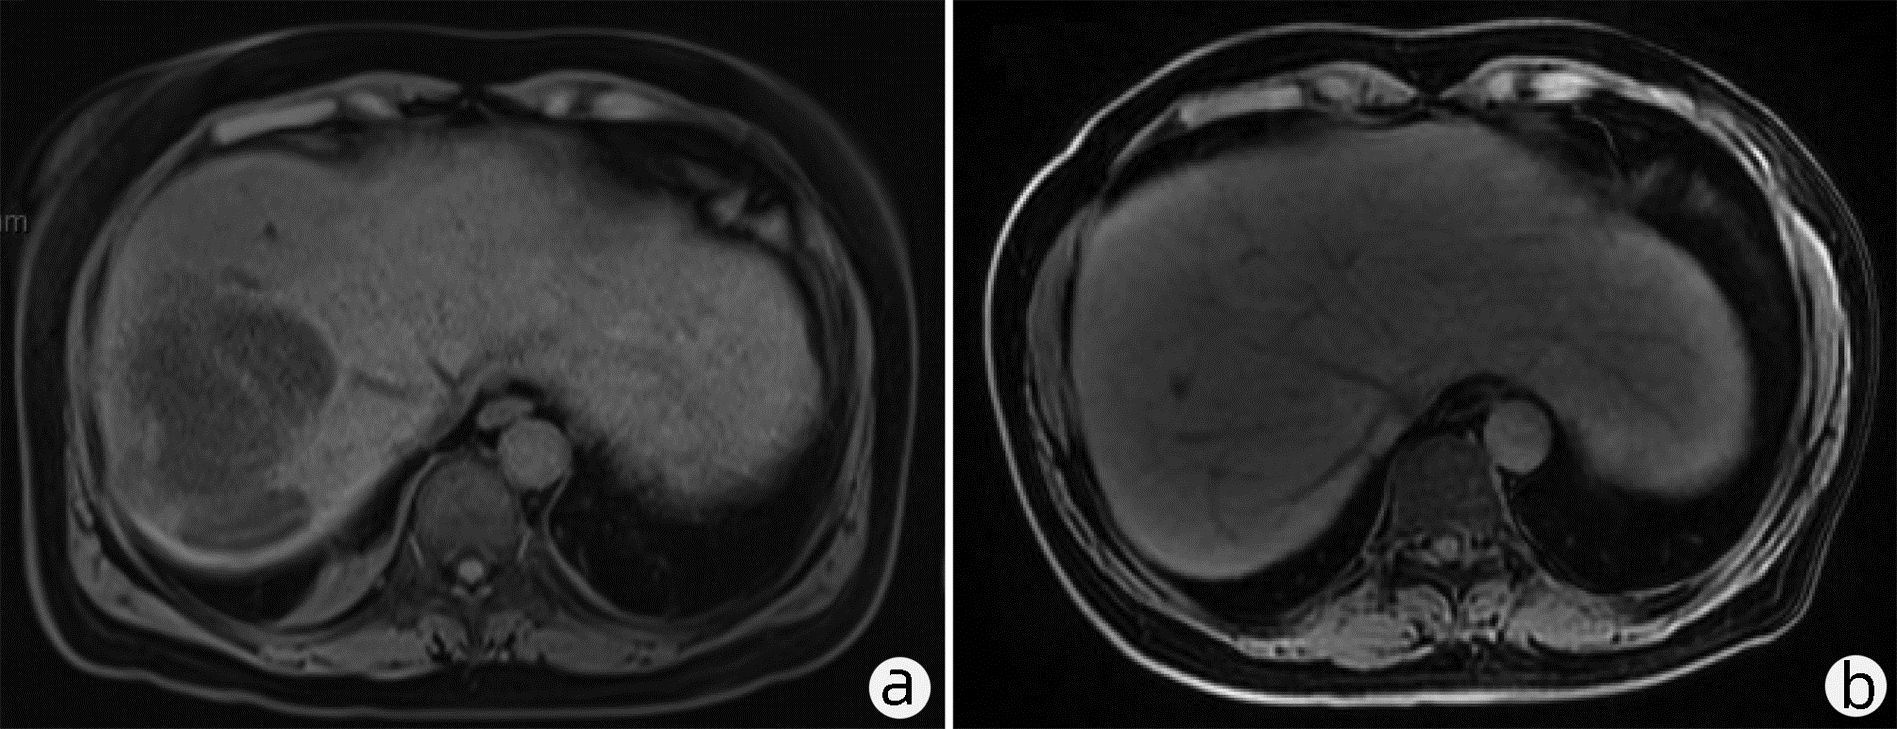

A case report of successful diagnosis and treatment of hepatic sinusoidal obstruction syndrome

Wenqian GENG, Hao ZHU, Xin YANG, Wanyu LI, Fang XU, Yanjun CAI, Pujun GAO

2023, 39(2): 397-400. DOI: 10.3969/j.issn.1001-5256.2023.02.023

Abstract(1481) HTML (483) PDF (2418KB)(142)

Abstract: